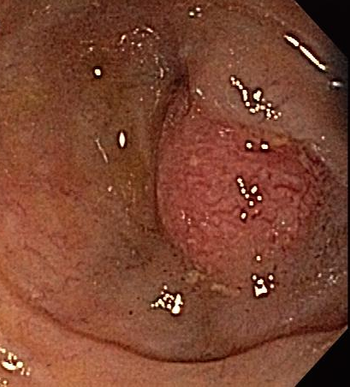

A 28-year-old man reports pain on swallowing of a week's duration. He is otherwise in good health. Upper endoscopy and tissue biopsy reveal the cause. What do you see?

This patient's presenting symptom, in the context of his overall health, should prompt orders for which follow-up studies?

Test your knowledge of this GI finding with questions on diagnosis, laboratory screening, and removal.